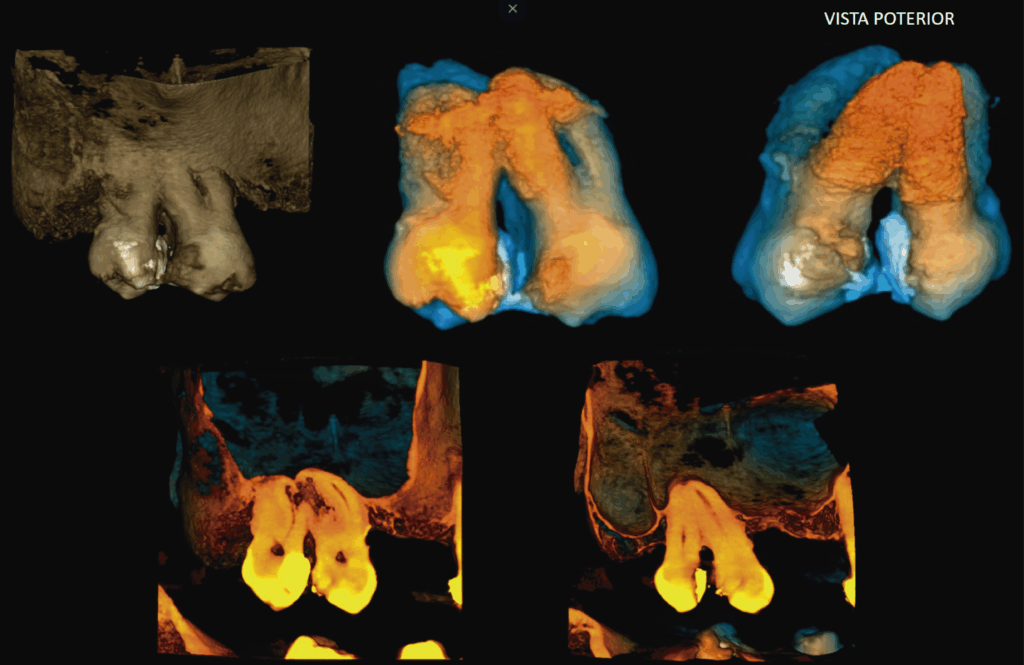

A la evaluación de la tomografía de campo reducido con un tamaño de voxel de 0.75 mm se pudo observar el seno maxilar derecho con presencia de contenido isodenso compatible con sinusitis de origen no odontogénico. Asimismo, se evidencio una reabsorción radicular externa por aposición que compromete la raíz mesiovestibular de la pieza 18 y la raíz distovestibular de la pieza 17 y que se extendía hasta conducto pulpar (visto en cortes tangenciales y axiales) y finalmente se observó hipercementosis de ambas piezas y ausencia del espacio para el ligamento periodontal perirradicular a predominio de zona interproximal de las raíces palatinas compatible con concrescencia.

RECONSTRUCCIÓN 3D